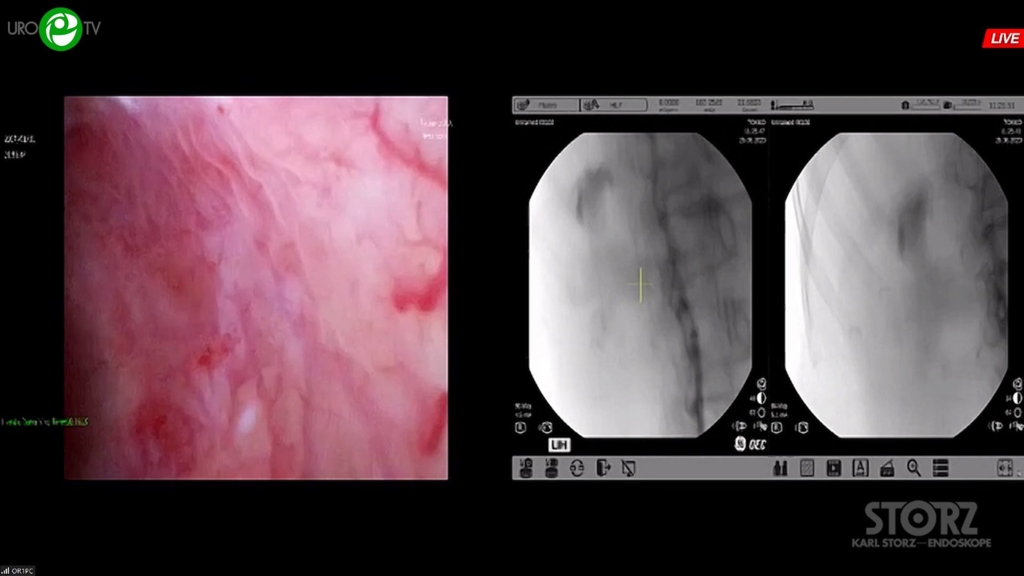

Мартов А.Г. - Комбинированная интраренальная хирургия с использованием технологии микроперк

01 сен 2023

Мочекаменная болезнь